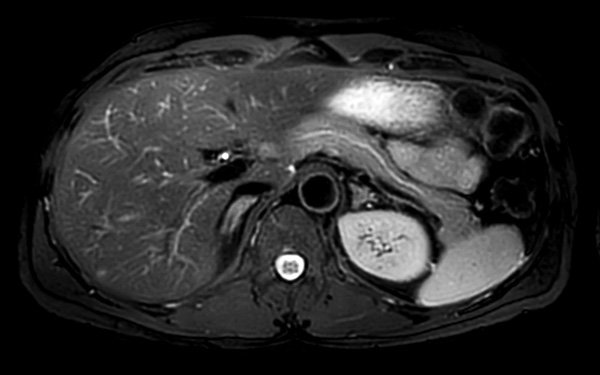

Axial mDIXON (W, IP, OP, F)